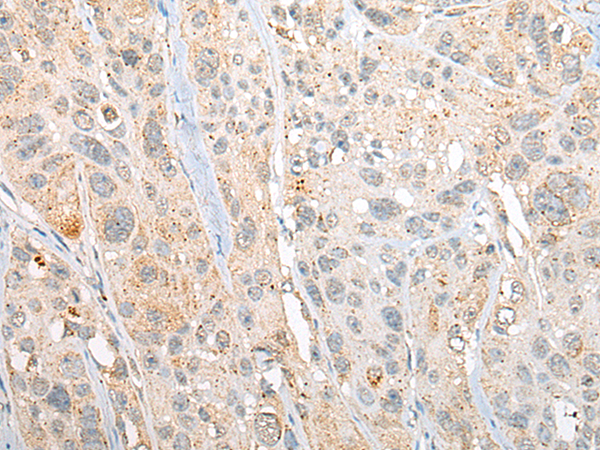

分类: 科研抗体货号: P13206别名:应用: IHC反应种属: Human, Mouse, Rat